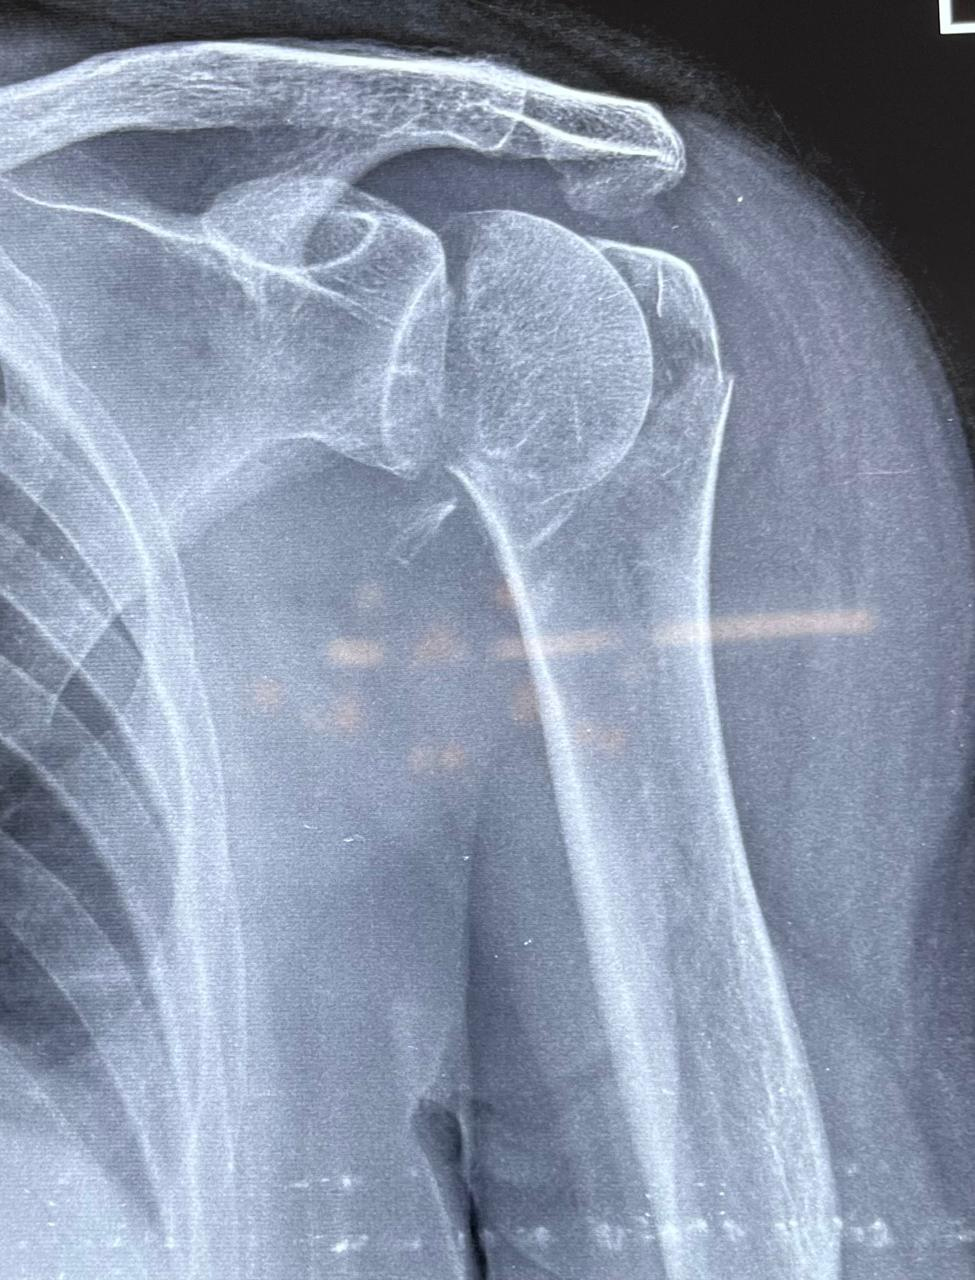

X-ray left shoulder external rotation ap view of SMT Indumati in 414A